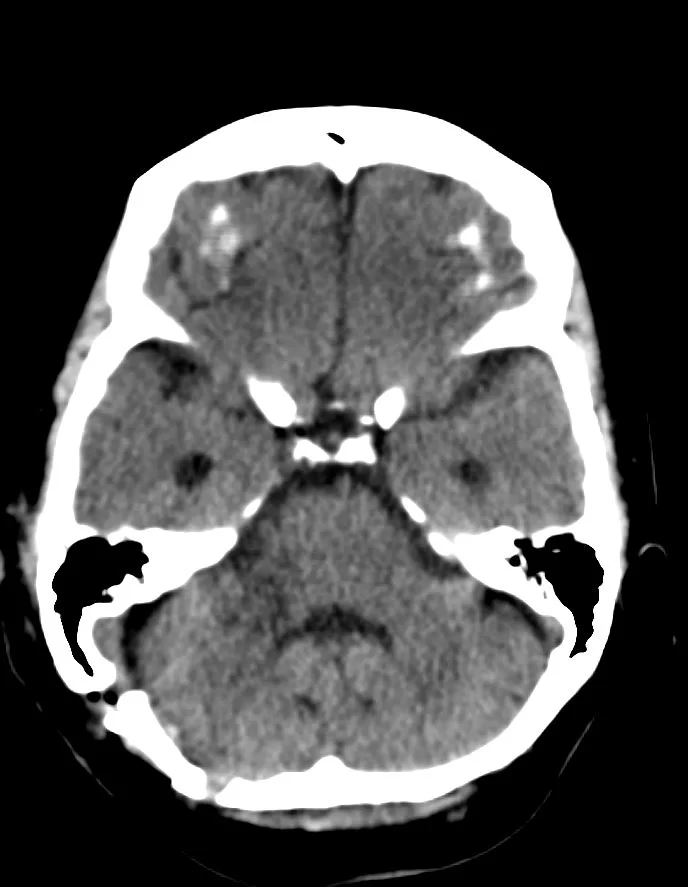

Η μαγνητική τομογραφία εγκεφάλου ανέδειξε χωροκατακτητική εξεργασία στη δεξιά γεφυροπαρεγκεφαλιδική γωνία συμβατή με ακουστικό νευρίνωμα (αιθουσαίο σβάννωμα) και πίεση επί του στελέχους (Koos IV).

Η ασθενής υπεβλήθη σε δεξιά οπισθοσιγμοειδική κρανιοτομία και ολική αφαίρεση της βλάβης.

Τα ακουστικά νευρινώματα είναι χειρουργικά απαιτητικοί όγκοι, λόγω της εγγύτητάς τους με πολλά εγκεφαλικά νεύρα και κυρίως με το προσωπικό νεύρο. Στο συγκεκριμένο περιστατικό υπήρχε πίεση επί του στελέχους και ο όγκος –αν και καλοήθης- ήταν αρκετά μεγάλος, οπότε η ένδειξη για χειρουργείο ήταν σαφής.